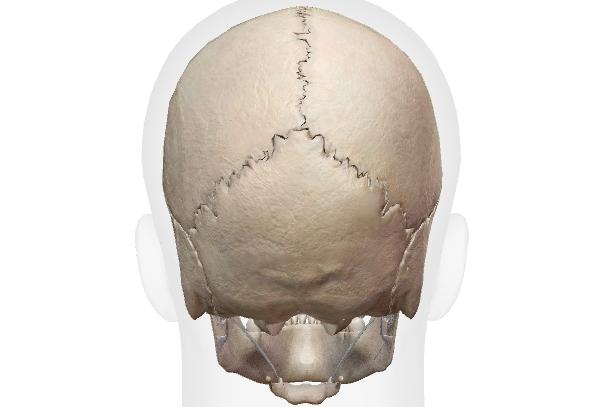

線維性関節(線維性連結)

コラーゲンなどを成分とする強靭な繊維の束によって連結されている部位。

頭蓋の 縫合、上下顎骨と歯の釘植(ていしょく)がそれにあたります。

歯周病菌などに侵されたら歯は抜けますが、それ以外では当然動かない(動かせない)不動関節です。